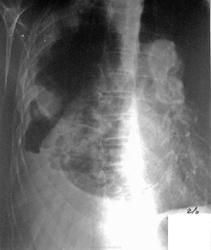

После плевральной пункции проведено контрольное рентгенологическое обследование.

Не могу разобраться, что за уровни жидкости на рентгенограммах при контрольном исследовании, возможно жидкость между плевральными спайками? Какова природа гидроторакса? Очень интересно ваше мнение…

а на боковой если посмотреть в переднем отделе огк, это что за полость. а так тоже за зло, с метестазами

Мне тоже не ясно это за полость, вопрос с образованием решен, но что за уровни жидкости?

Развитие пневмогидроторакса после плевральной пункции, на фоне спаечного процесса?